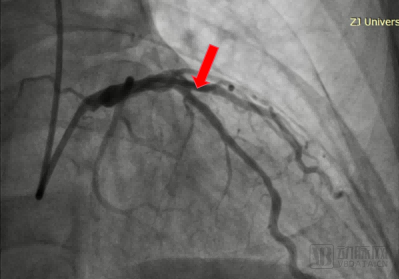

手术过程中,王建安院士团队先使用3.0×13mm规格的棘突球囊预扩张病变血管。随后使用3.5×15mm的矩正冠状动脉血管重塑导管以10atm扩张血管,并启动激光治疗。术后造影显示扩张效果良好,无残余狭窄无夹层,TIMI血流3级,手术圆满完成。

患者LAD术后造影